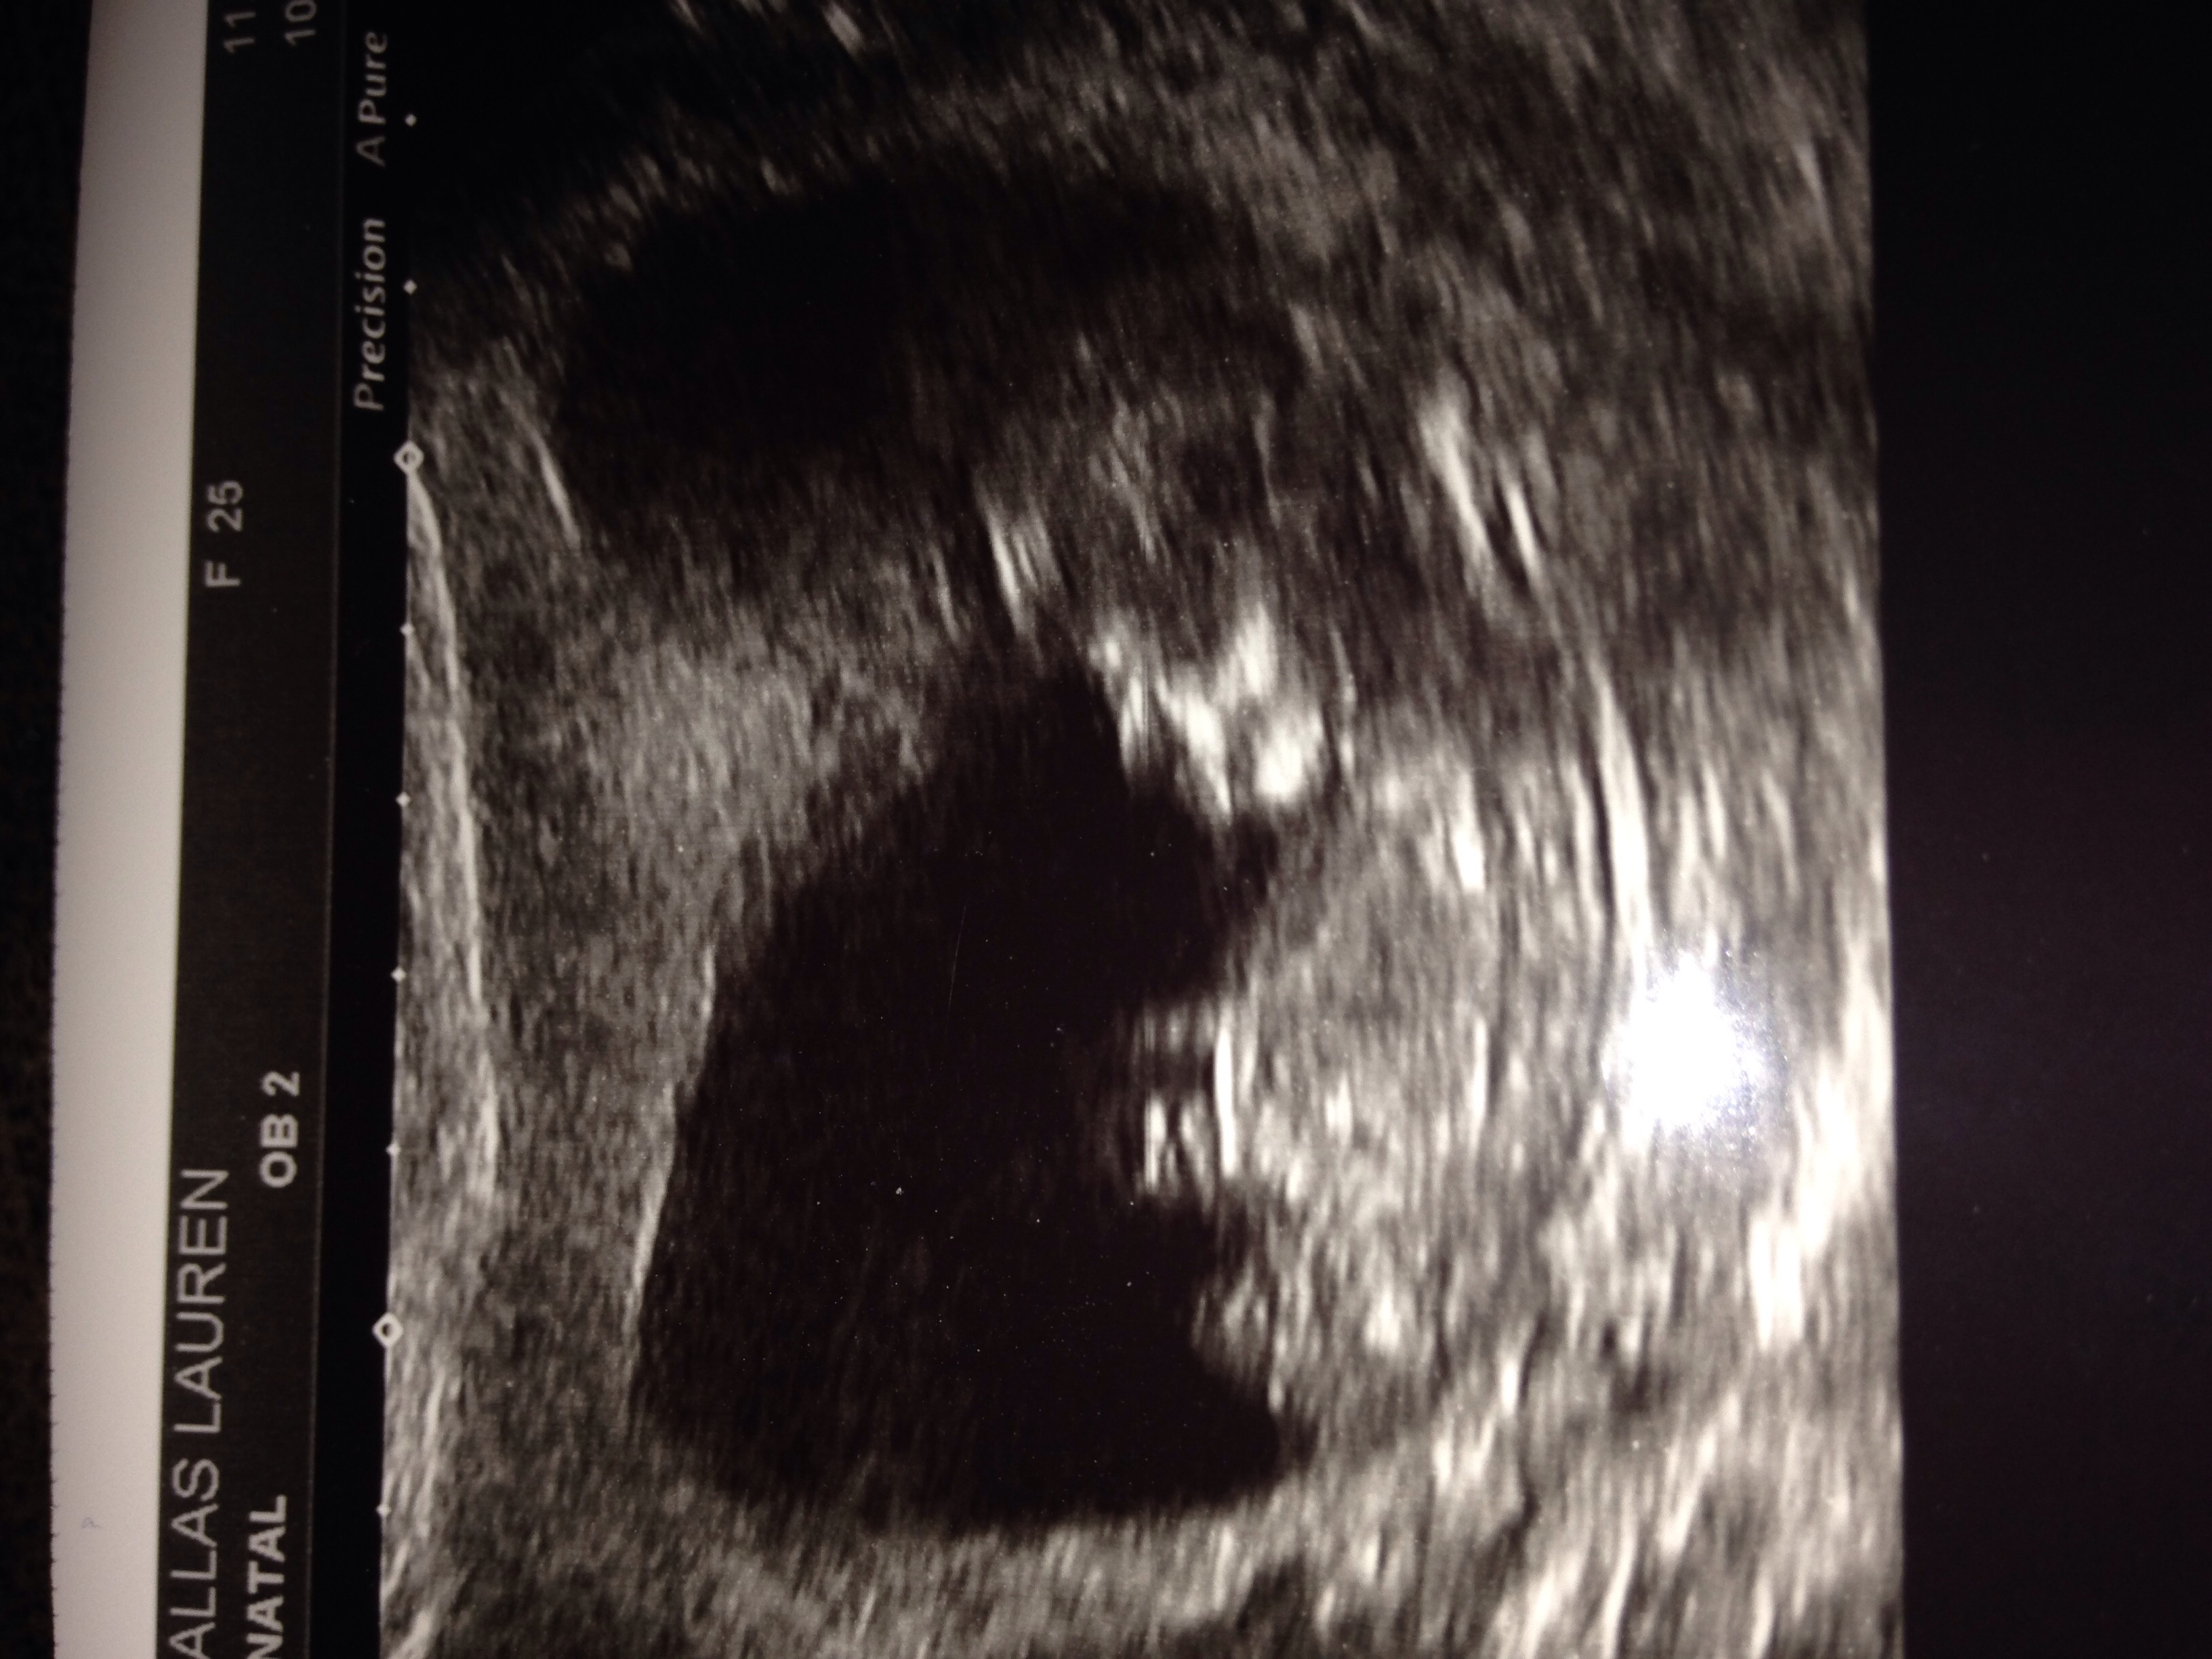

This is my 3rd child I'm eager to find out people's opinions be it nub / skull theory ? Pic from 12week +2 ... Also have a pic from 6week +2 which may be good for ramzi predictions? I can't even find nub so any help greatly appreciated xxx